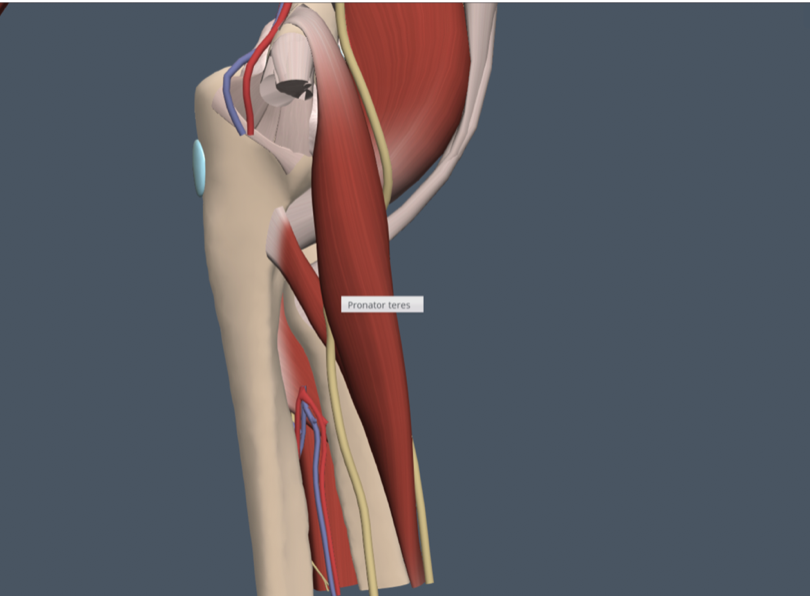

Tommy John Injury: Journey Back to Throwing after a UCL Injury

Anatomy of Ulnar Collateral Ligament (UCL) Originating on the anteroinferior surface of the medial epicondyle of the humerus and inserting onto the sublime tubercle of ...